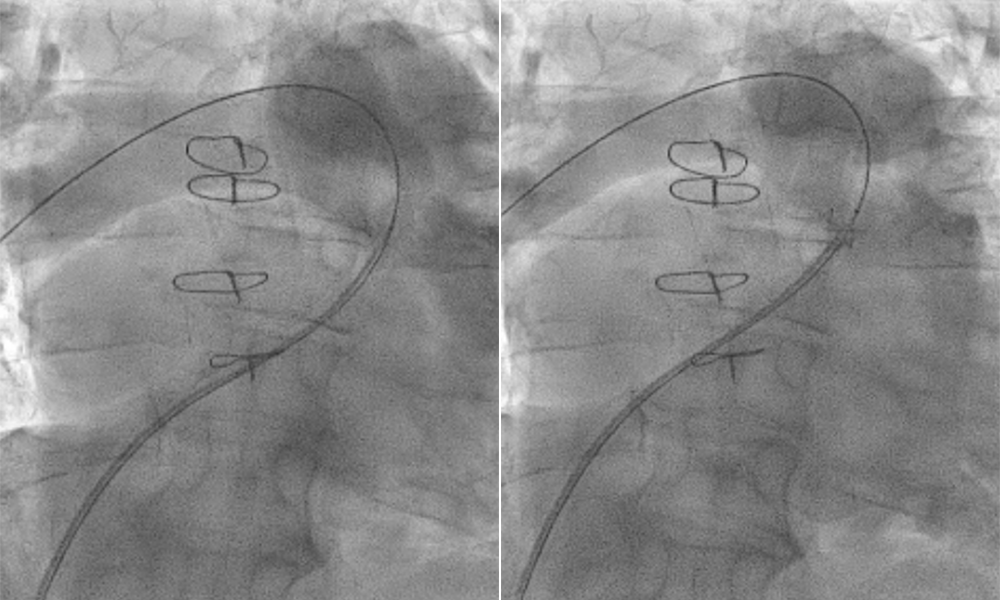

Angiogram of the right pulmonary artery (RPA) during systole (left) and diastole (right) showing a severely dilated RPA that is dynamic and enlarges with systole.